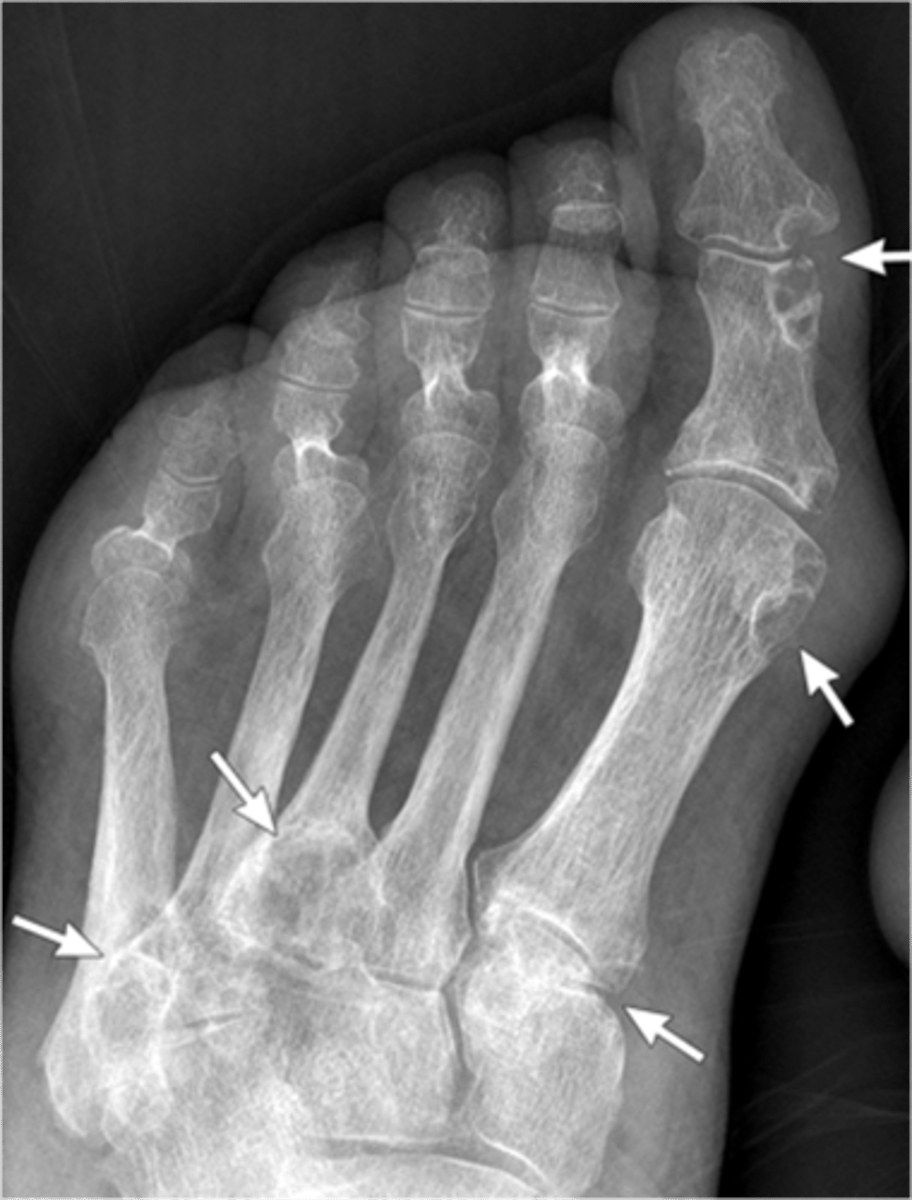

- Dense soft tissue tophi (swelling)

- Bone erosions

- Overhanging margin sign

- Secondary degeneration

- 1st MTP MC joint

State the radiographic findings of gout